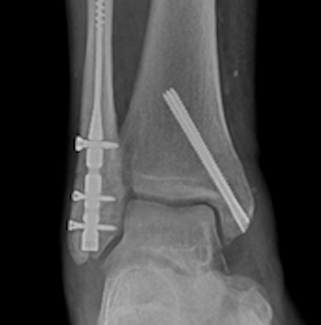

Ankle Fracture Fixation

04/01/2026

Alexa Bykowski, DPM; Brian Burgess, DPM, FACFAS

Ankle fracture management is increasingly guided by mortise stability and patient factors, not simply fracture pattern or the number of malleoli involved. Even subtle talar malalignment can dramatically alter tibiotalar contact mechanics and...

This report presents the unique perspective of a podiatric physician integrated into the surgical management of an unstable ankle fracture, performed by an orthopedic trauma surgeon. The experience highlights both the technical nuances of...